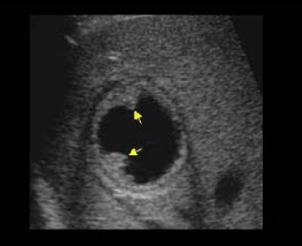

Identify this image.

Early stage echinococcal or Hydatid cyst